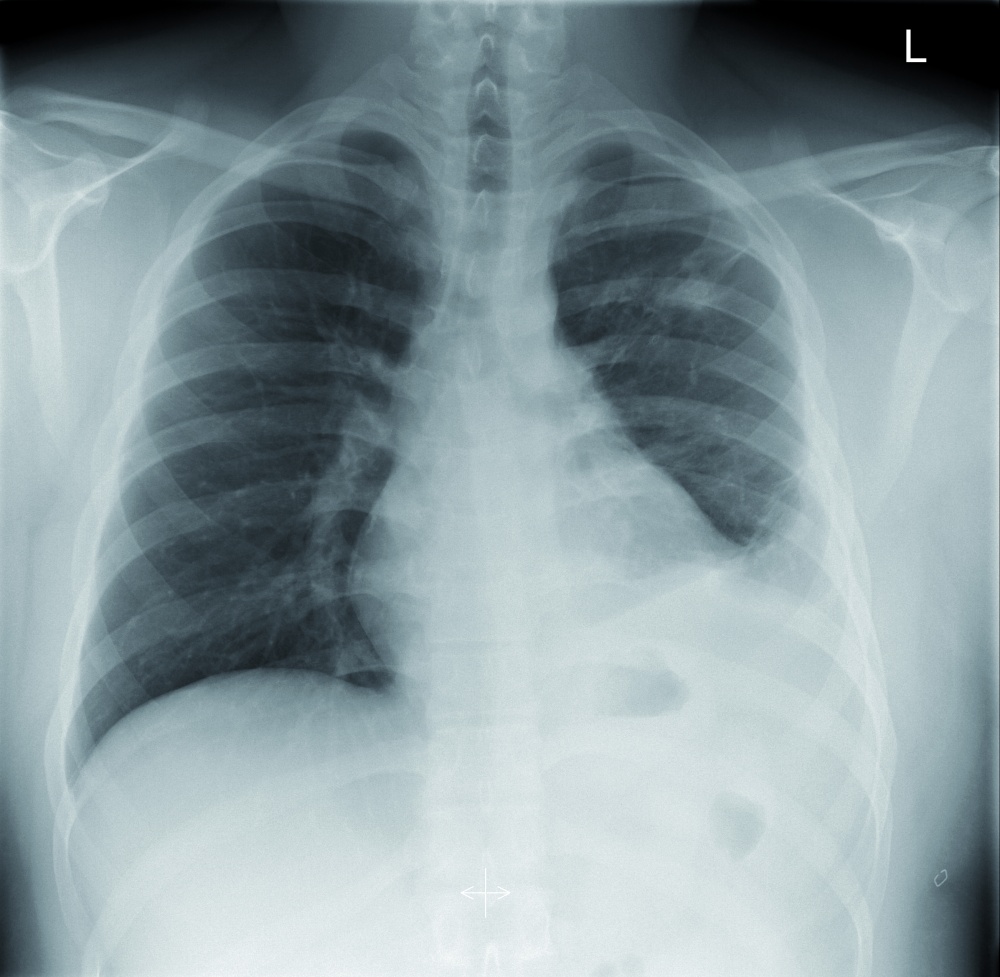

In der klinischen Untersuchung zeigte sich inspektorisch eine 4 x 3 cm große penetrierende Thoraxverletzung mit Verbrennungen II. Grades links parasternal (Abbildung 1) ohne feststellbare Austrittssverletzung am Rücken. Linksapikal war das Atemgeräusch vermindert, die Herztöne waren rein, rhythmisch und ohne pathologische Geräusche. Noch am Unfallort wurde eine Thoraxdrainage gelegt, die bis zur Aufnahme nur wenig venöses Blut gefördert hatte. Die Notfallsonographie (FAST[1]) und der Bodycheck im Rahmen des Primary Survey (ATLS®[2]) waren ansonsten unauffällig. Labordiagnostisch zeigten sich keine Auffälligkeiten, insbesondere kein Hb-Verlust und eine normwertige Gerinnung. Sämtliche Einzelteile des Ventils konnten am Unfallort asserviert werden, so dass die Verletzung allein durch das unter hohem Druck stehende Hydrauliköl verursacht worden war.

CT-Thorax

Die CT-Diagnostik zeigte eine sagittal verlaufende perforierende Verletzung des Lungenoberlappens links mit einer tiefreichenden Weichteilverletzung der ventralen Thoraxwand (Abbildung 2). Das Herz und die großen mediastinalen Gefäße waren unbeeinträchtigt. Ein Fremdkörper konnte auch CT-morphologisch ausgeschlossen werden.